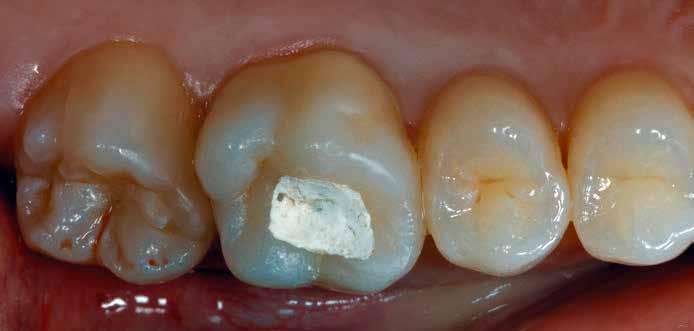

Egy 31 éves férfi páciens jelentkezett a jobb felső első molárisából kiinduló, reverzíbilis pulpitisre utaló tünetekkel. A klinikai vizsgálat során meglévő okkluzo-palatinális ezüsta-

malgám restauráció volt észlelhető, valamint szekunder caries mesiálian, a marginális gerinc kavitációjával együtt (10. ábra). A mesio-bukkális csücsök csúcsán kopási fazetta volt látható; a fog egyébként klinikailag és radiológiailag épnek bizonyult. A tájékoztatáson alapuló beleegyezést követően a kezelési terv II. osztályú, háromfelszínű direkt kompozit restauráció volt.

2. ábra: A páciens egy nem megfelelő I. osztályú ezüstamalgám töméssel és II. osztályú szuvasodással jelentkezett. A fog izolálása kofferdám alkalmazásával történt.

3. ábra: A preparálás, a bondozás és a kompozit felvitele után. (Megjegyzés: némi kompozit túlfolyás látható a mesiális doboz axiális falain).